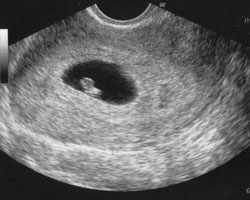

Mostramos-te, em seguida, um vídeo e uma ecografia correspondentes à 6ª semana. É impressionante a rapidez com que se desenvolve o embrião.

Ecografia de 6 semanas